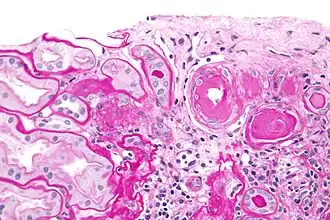

| Micrograph showing renal arterial hyalinosis – pink ring right-of-centre. PAS stain. | |

In the kidneys, as a result of benign arterial hypertension, hyaline (pink, amorphous, homogeneous material) accumulates in the walls of small arteries and arterioles, producing the thickening of their walls and the narrowing of the arterial openings, a process known as arteriolosclerosis. The resulting inadequate blood flow produces tubular atrophy, interstitial fibrosis, and glomerular alterations (smaller glomeruli with different degrees of hyalinization – from mild to sclerosis of glomeruli) and scarring around the glomeruli (periglomerular fibrosis). In advanced stages, kidney failure will occur. Functional nephrons[6] have dilated tubules, often with hyaline casts in the opening of the tubules. Additional complications often associated with hypertensive nephropathy include glomerular damage resulting in protein and blood in the urine.

In benign nephrosclerosis, the changes occurring are gradual and progressive, however, there can be sufficient kidney reserve capacity to maintain adequate kidney function for many years.[10] The large renal arteries exhibit intimal thickening, medial hypertrophy, duplication of the elastic layer. The changes in small arterioles include hyaline arteriolosclerosis (deposition of hyaline, collagenous material), which causes glomerular collapse (wrinkling and thickening of capillary basement membranes and collapse of capillary lumen) and solidification (glomeruli exhibit sclerosis and increase in mesangial matrix). The degree of scarring correlates with the degree of glomerular filtration deficit.